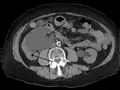

CT scan of bilateral hydronephrosis due to a bladder cancer